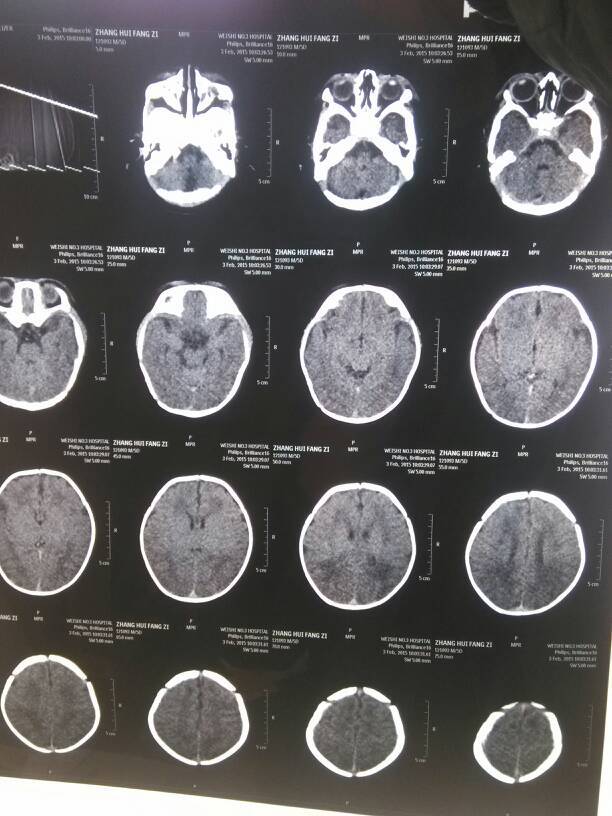

刚出生时说缺氧,羊水3度污染,肺炎,5天后大夫做了个ct,检测说ct值有点低,ct值14,目前在妇 刚出生时说缺氧,羊水3度污染,肺炎,5天后大夫做了个ct,检测说ct值有点低,ct值14,目前在妇幼打的补脑针,想问下医生这个值可以上升吗?需要多长时间?后期有影响吗? 点击展开 kakala2012 2015-02-05 16:57 为您推荐: 其他回答 祝宝宝健康 流年。。 2015-02-05 17:46 不用做高压氧么 宝乐妈 2015-02-05 17:12 祝宝宝健康成长 ωǒ愛老ぺ公 2015-02-05 17:05 唉!做妈妈真是有操不完的心,祝宝宝健健康康的 宣仔 2015-02-05 17:03 问问专业人士比较放心 dai两熊孩子 2015-02-05 16:59 加载更多 相关问题 新生儿出生当天被检查出脑出血,轻度缺氧,肺炎 其中羊水三度污染 请问到底是怎么回事?大家帮帮忙啊! 新生儿羊水三度污染会导致新生儿肺炎吗 新生儿羊水三度污染,引起新生儿肺炎?